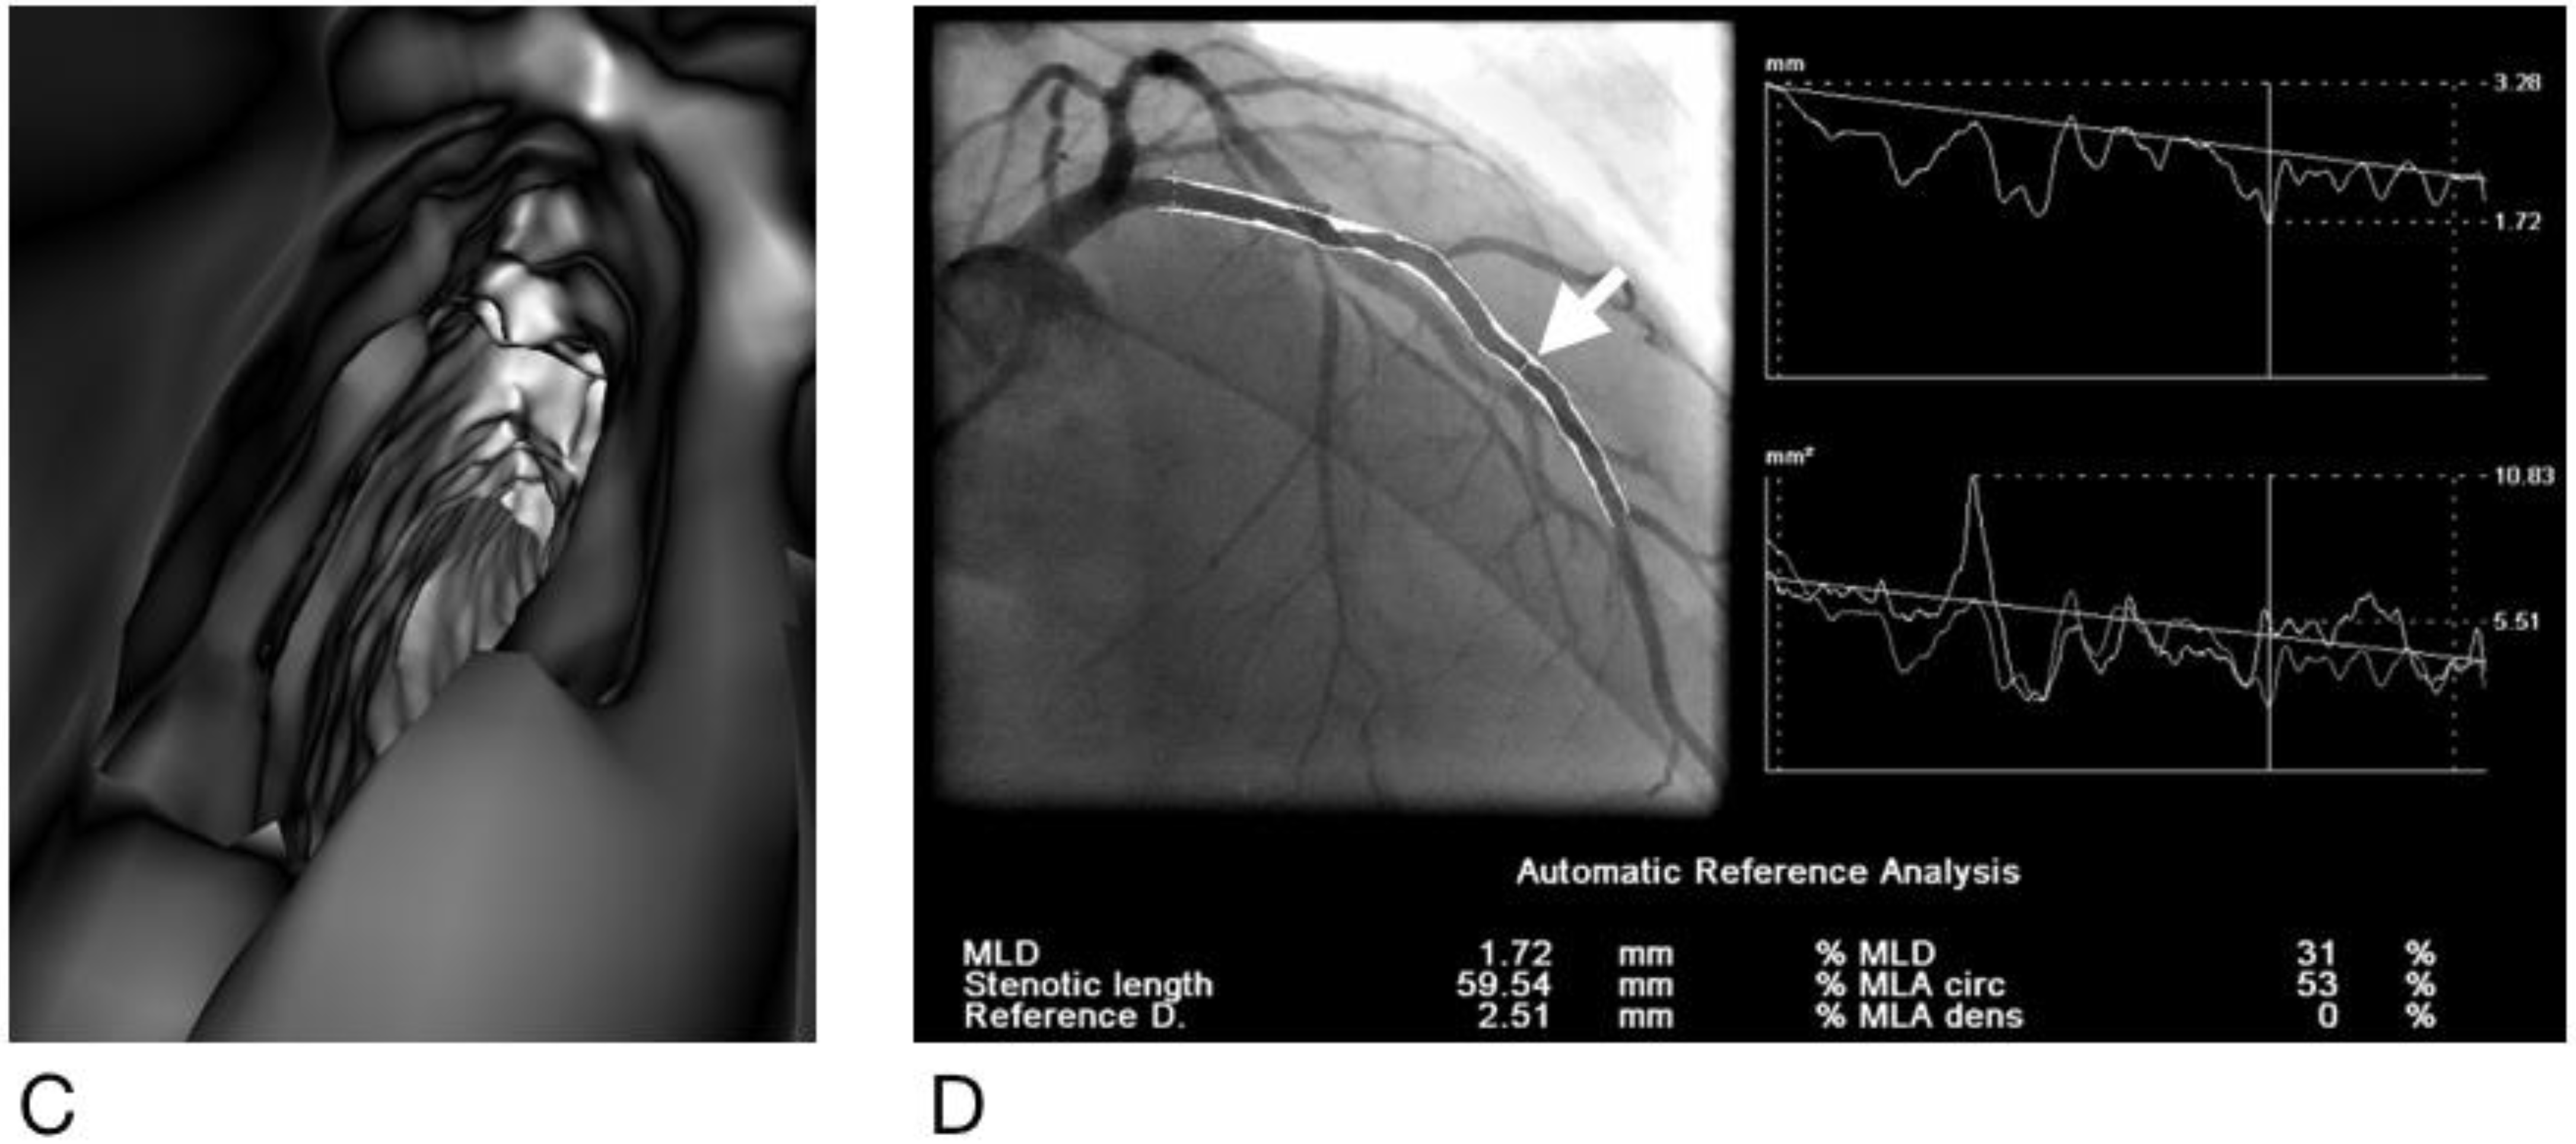

- Sun, Z.; Dimpudus, F.J.; Nugroho, J.; Adipranoto, J.D. CT virtual intravascular endoscopy assessment of coronary artery plaques: A preliminary study. Eur. J. Radiol. 2010, 75, e112–e119. [Google Scholar] [CrossRef] [PubMed]

- Xu, L.; Sun, Z. Virtual intravascular endoscopy visualization of calcified coronary plaques: A novel approach of identifying plaque features for more accurate assessment of coronary lumen stenosis. Medicine 2015, 94, e805. [Google Scholar] [CrossRef] [PubMed]

- Sun, Z.; Xu, L. CT virtual intravascular endoscopy in the visualization of coronary plaques: A pictorial essay. Curr. Med. Imaging Rev. 2017, 13, 154–161. [Google Scholar] [CrossRef][Green Version]

- Sun, Z. Coronary CT angiography in coronary artery disease: Correlation between virtual intravascular endoscopic appearances and left bifurcation angulation and coronary plaques. Biomed. Res. Int. 2013, 2013, 732059. [Google Scholar] [CrossRef]